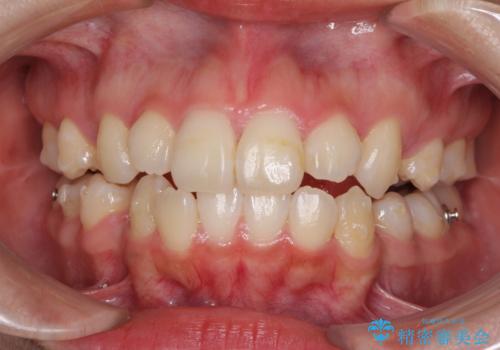

抜歯矯正による口元の改善にはワイヤー矯正が望ましいのですが、ダンサーとしての仕事を行っているため、インビザラインにて治療を行うこととしました。

インビザラインによる矯正治療は、どれだけマウスピースを外す時間を短くできるかが成功の鍵となりますが、抜歯矯正ではよりシビアに要求されます。

こちらの患者様は、1日22時間以上を厳守してくださり、3年強で終えることができました。